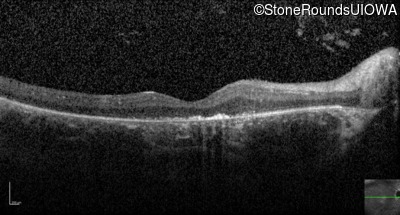

Optical Coherence Tomography - Left - Hand Motion 6" sc

Exemplar / OCT Stack